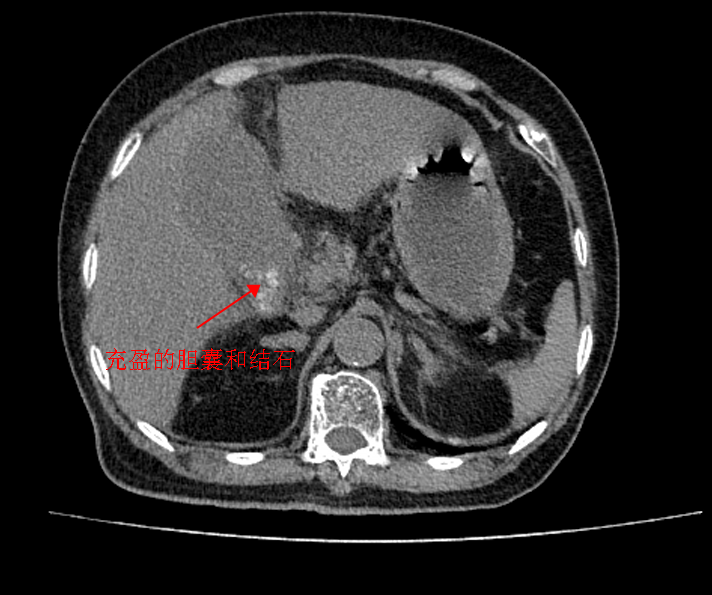

65岁的汤阿姨,就诊前两天,突感右上腹疼痛,以为是吃坏肚子了,并未重视,但随着时间的推移,汤阿姨腹痛不但没有缓解,反而更严重了。连续两天的持续胀痛、恶心呕吐,让汤阿姨深感煎熬,实在受不了才到我院就诊。经检查,被确诊为“胆囊结石伴胆囊炎”,感染指标严重超标,情况十分危急,需立即手术。

肝胆腺体外科主任马天如副主任医师结合患者病史及相关检查,综合评估认为,患者胆囊已出现坏疽,有急诊手术指征。汤阿姨得知病情后十分紧张——本身患有高血压和糖尿病,她担心手术风险大、恢复困难。

在了解到汤阿姨的顾虑后,科室团队全面细致地评估,在与汤阿姨及家属充分沟通后,团队为汤阿姨实施了“腹腔镜下胆囊切除术”。术中发现胆囊已明显坏疽,团队在腹腔镜下精准操作,顺利切除病变胆囊。术后,结合中西医结合康复疗法,汤阿姨第2天即可下床活动,第5天康复良好,顺利出院,整个住院时间仅为5天。